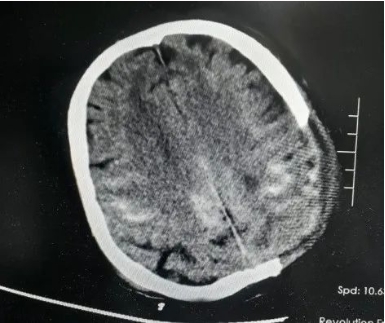

5月1日,青岛西海岸新区中医医院急诊科接诊了深度昏迷、瞳孔散大,生命体征极其微弱的宋先生。据目击者描述,其被发现时已倒在路边,生命垂危。急诊团队迅速启动抢救流程:气管插管、建立静脉通路维持生命体征,颅脑CT显示“颅骨骨折、大量硬膜外血肿、脑疝”。

“必须分秒必争!”外五科主任侯鹏志当即联合麻醉科、输血科组建抢救团队,制定“精准止血+血肿清除”手术方案。术中“险象环生”,开颅瞬间,破裂的上矢状窦喷涌出血,患者血压骤降至52/32mmHg,麻醉团队迅速予升压药物泵入并加压输血以维持血压稳定!大量出血导致手术视野模糊,稍有不慎就可能引发“灾难性”后果,在模糊视野中主刀医师精准分离粘连组织,以毫米级操作修补窦壁、清除血肿……4小时鏖战后,出血成功控制,脑组织压迫解除,患者生命体征趋稳!